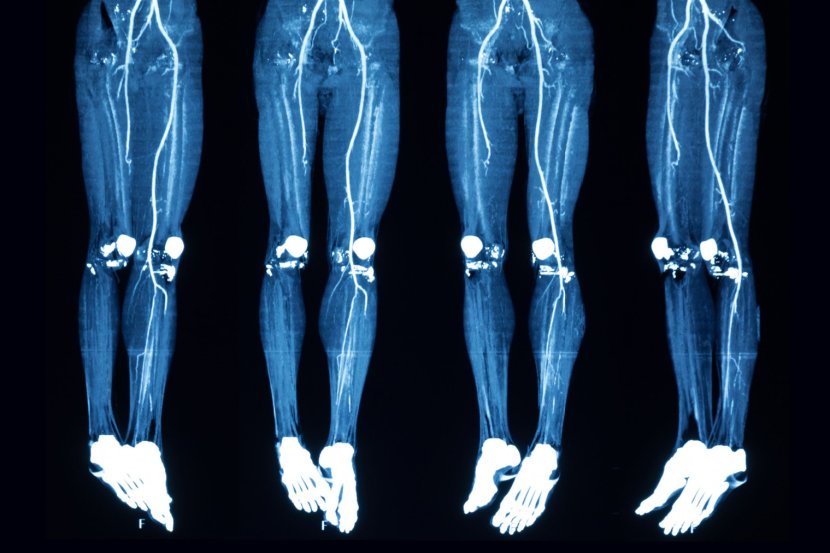

Dijagnostika je jednostavna i uključuje sledeće metode: tzv. test provocirane hiperemije, dopler sonografiju, arteriografiju i MSCT-arteriografiju (multislajsna kompjuterizovana tomografija).